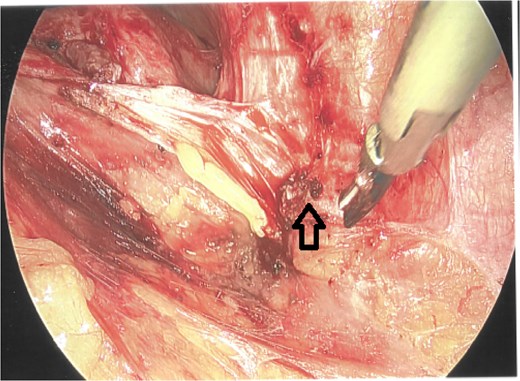

The wound healed well post-operatively. The patient returned for planned excision of remaining fistula (Fig. 3) and primary closure of the skin. Her postoperative follow-up remains unremarkable with no further wound complications.